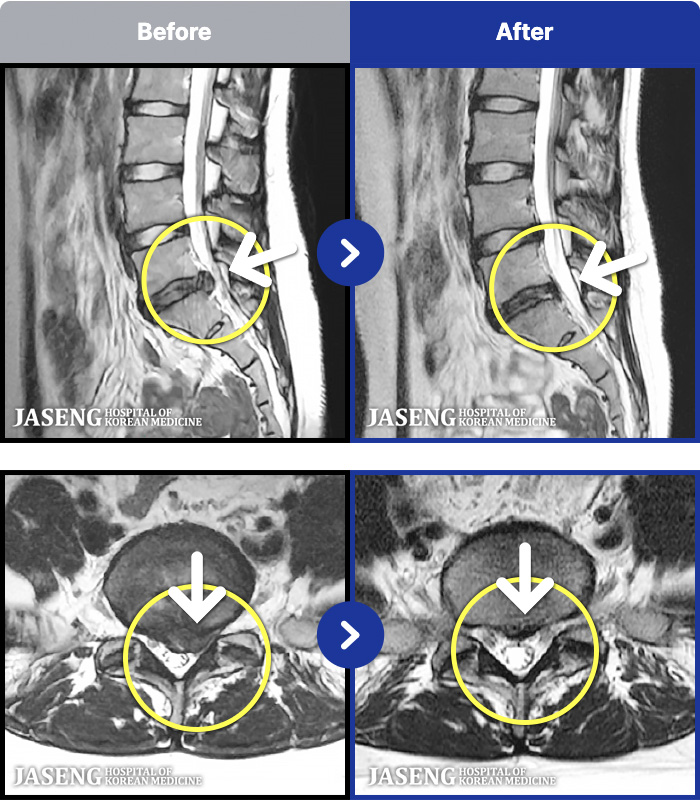

- MRI ġ

MRI ġ

191 MRI ũ ʸ Ȯϼ.